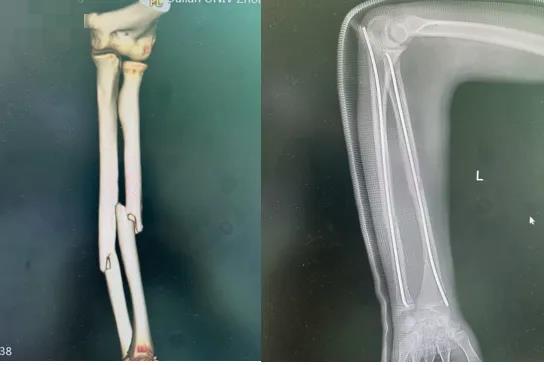

这是一种专门为儿童设计的骨折微创手术。医生仅在骨折肢体远端做两个不到2厘米的小切口,将两根具有良好弹性的钛合金髓内钉置入骨髓腔,像支架一样从内部将骨折端固定(见示意图)。它巧妙利用了“三点支撑”的力学原理,既能稳定骨折,又允许微动,特别适合儿童骨骼的生理特点。